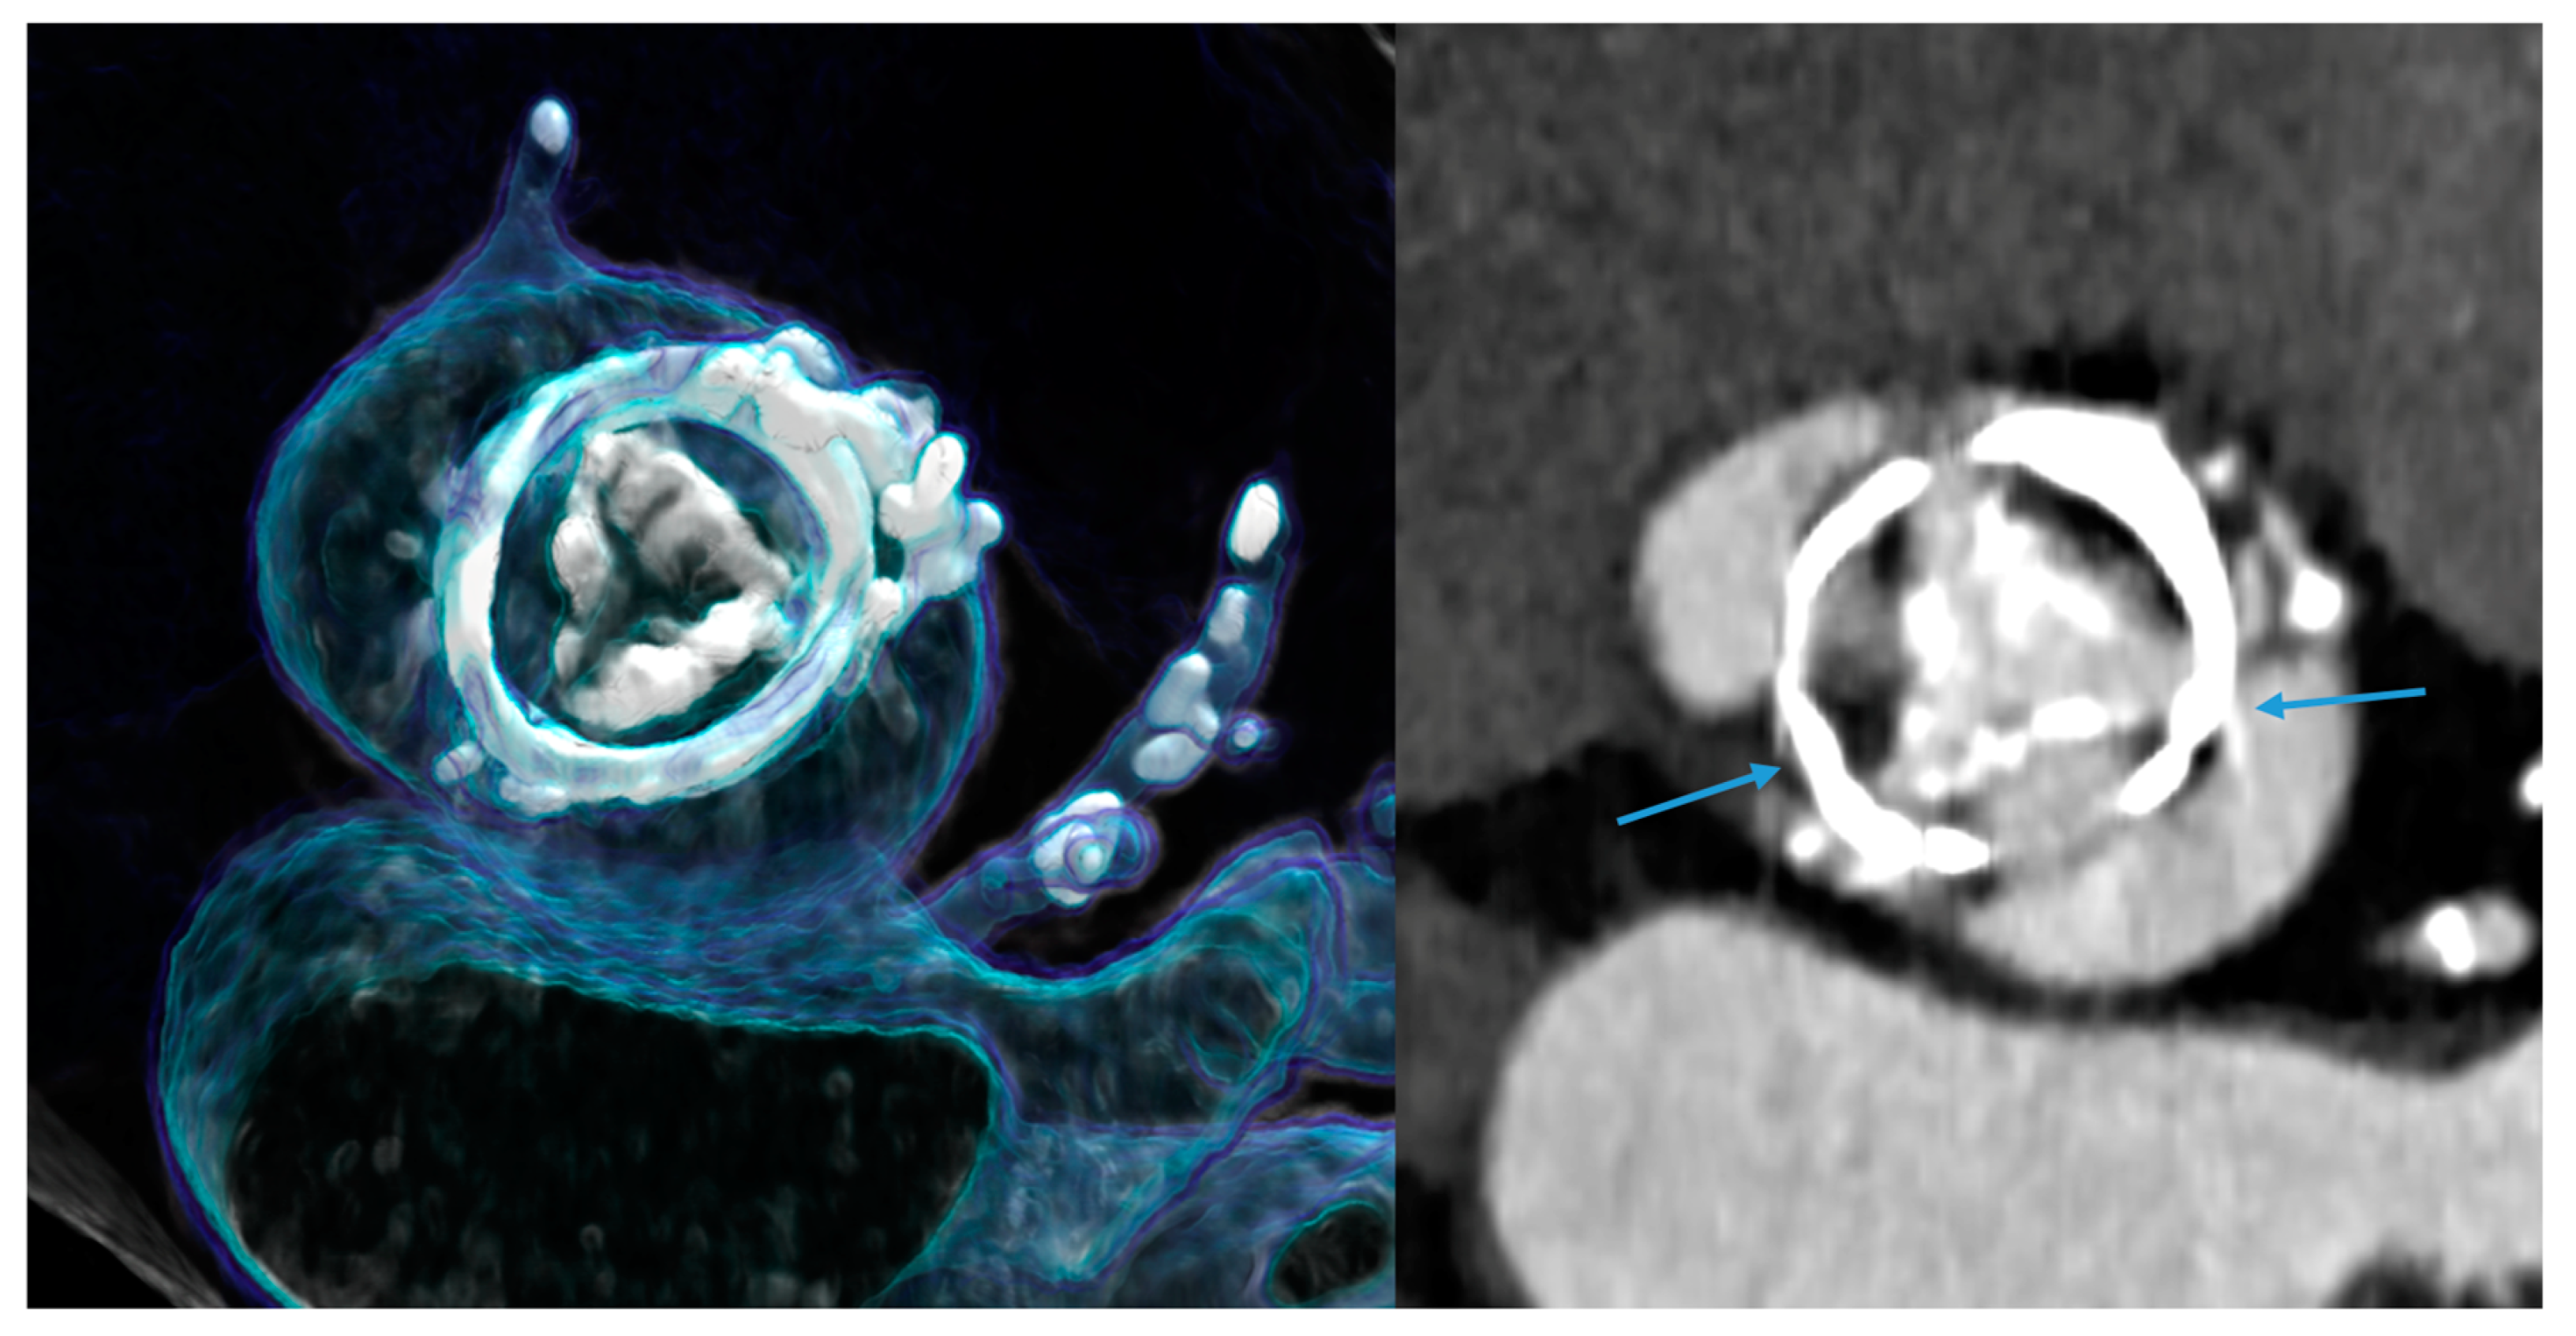

3.2. Is the Evaluation of Coronary Stents More Accurate with PCD-CT?

| STENTS—in vivo studies | ||

| Hagar et al. [20] | 44 (n = 5 ISRs) | 5 (100%) ISRs detected vs. ICA |